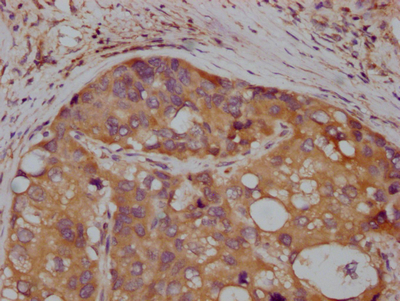

IHC image of CSB-RA983271A0HU diluted at 1:100 and staining in paraffin-embedded human liver cancer performed on a Leica BondTM system. After dewaxing and hydration, antigen retrieval was mediated by high pressure in a citrate buffer (pH 6.0). Section was blocked with 10% normal goat serum 30min at RT. Then primary antibody (1% BSA) was incubated at 4℃ overnight. The primary is detected by a Goat anti-rabbit IgG polymer labeled by HRP and visualized using 0.05% DAB.